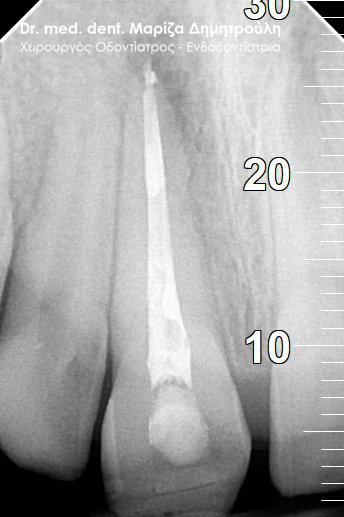

Root canal treatment

AFTER